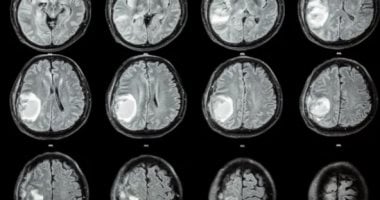

أغرب حكايات الطب.. إزالة جنين من دماغ طفلة أمريكية عمرها عام

القاهرة: «السفير» في حالة نادرة للغاية ، قام الأطباء بإزالة الجنين الجراحي من دماغ فتاة أمريكية واحدة ، ووجد الأطباء…